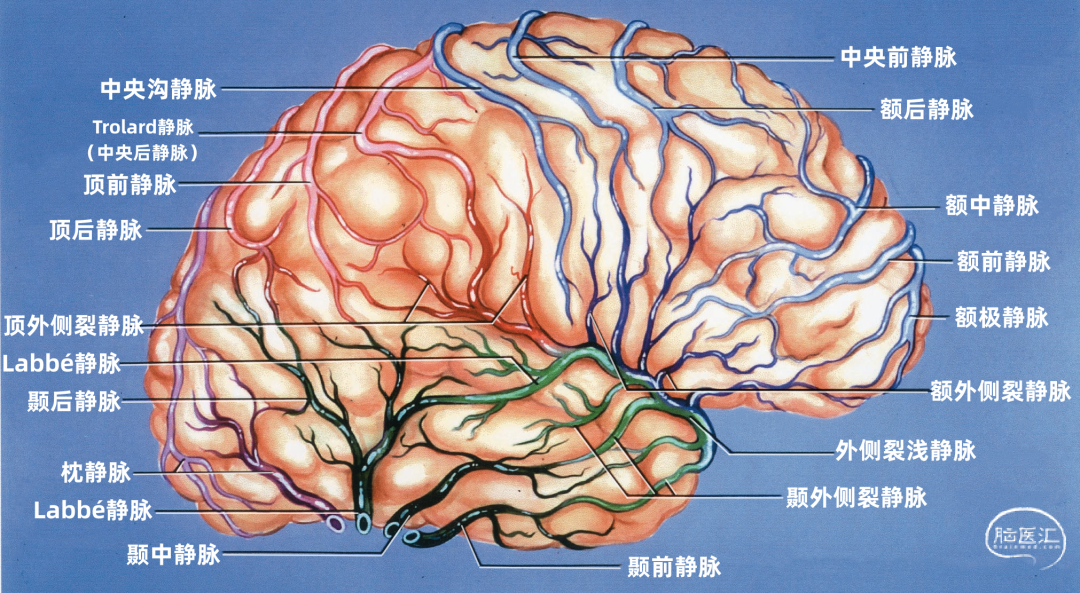

根据引流半球外侧面、内侧面或底面,皮层静脉分为三组。三个面的皮层静脉可依据其引流的脑叶和皮层区进一步细分。皮层静脉引流区域和方向如下: 额叶外侧面(蓝色)由额极静脉、额前静脉、额中静脉,额后静脉、中央前静脉、中央静脉、额外侧裂静脉引流。 顶叶外侧面(黄色)由中央静脉、中央后静脉、顶前静脉、顶后静脉、顶外侧裂静脉引流。 颞叶外侧面(绿色)由颞前静脉、颞中静脉、颞后静脉、颞外侧裂静脉引流。

大脑外侧面的静脉引流方向

额叶外侧面的静脉按引流方向由两种蓝色标出:浅蓝色为上升的静脉。进入上矢状窦。深蓝色为下降的静脉,进入外侧裂浅静脉。

升支静脉包括额极静脉,额前静脉,额中静脉、额后静脉、中央前静脉、中央静脉。降支包括额外侧裂静脉。

顶叶外侧面的静脉按引流方向由两种红色标出:浅红色为上升静脉,进入上矢状窦。深红色为下降静脉,进入外侧裂浅静脉。

升支静脉包括中央静脉、中央后静脉、顶前静脉、顶后静脉,Trolard静脉相当于大的中央后静脉。降支包括顶外侧裂静脉。

枕叶外侧面的引流静脉由紫色标出:它们主要是一些上升静脉,称为枕静脉,进入上矢状窦。一些小的枕静脉可能向下进入横窦和小脑幕窦。

颞叶外侧面的静脉按引流方向由两种绿色标出:浅绿色为上升静脉,进入外侧裂浅静脉。深绿色为下降支,进入小脑幕窦。

升支静脉是颞外侧裂静脉。降支包括颞前静脉、颞中静脉、颞后静脉

▼1.额叶

额叶的引流静脉分为外侧面组、内侧面组、底面组。外侧面组分为上升组,汇入上矢状窦;下降组,引流向外侧裂,进入外侧裂浅静脉。 上升组静脉包括额极、额前、额中、额后静脉,中央前静脉和中央沟静脉。这些静脉可能在回流至上矢状窦前与相邻的底面组、内侧面组的静脉汇合; 下降组由额外侧裂静脉组成。上升组引流的区域大于下降组。 额叶外侧面静脉及其引流区域如下:额极静脉引流额下回、额中回和额上回前部;额前、额中、额后静脉引流额极和中央前回之间的额叶前、中、后部凸面;中央前静脉引流中央前回下部、额下回盖部和邻近的额下、额中和额上回;中央Rolandic静脉引流中央沟附近的中央前回和中央后回;额外侧裂静脉引流额下回和邻近的额中回下部及中央前回下部。 额叶内侧面由弯曲的扣带沟分为内侧区和外侧区。额内侧静脉分为上升组进入上矢状窦;下降组进入下矢状窦或汇入行经胼胝体的静脉,最后进入基底静脉前端。上升组静脉由前内侧额静脉、中内侧额静脉、后内侧额静脉和旁中央沟静脉组成,它们是额上回内侧和邻近扣带回的主要静脉回流,一般向上弯曲走行,在半球上缘向外加入来自半球外侧组的静脉,然后注入上矢状窦。下降组静脉包括胼周前静脉、终板旁静脉和大脑前静脉。 额叶内侧面静脉及其引流区域如下:额前内侧静脉引流额极后方的扣带回和额上回;额中间内侧静脉引流胼胝体膝部前方的额上回和邻近扣带回的内侧面;额后内侧静脉引流胼胝体膝部上方的额上回和扣带回;旁中央静脉引流胼胝体体部上方的扣带回和邻近的旁中央小叶;胼周前静脉为成对的静脉,引流胼胝体膝部和嘴部,以及邻近的扣带回;大脑前静脉引流胼胝体嘴部以下至视交叉上缘之间的区域;终板旁静脉引流胼胝体嘴部下方的终板旁回和嗅旁回区域。 额下静脉组,引流额叶眶面区域,可分为前组和后组:前组流向额极注入上矢状窦;后组引流向后,在外侧裂内侧集中于前穿质表面,形成基底静脉。前组由额眶前静脉和额极静脉组成;后组由嗅静脉和额眶后静脉组成。 额下静脉及其引流区域如下:额眶前静脉引流直回前部和眶回前内侧部;额眶后静脉引流额叶眶面后部;嗅静脉引流嗅沟及其邻近的直回和内侧眶回。

▼2.顶叶

顶叶的静脉根据引流分为顶叶外侧面组和顶叶内侧面组。 引流外侧面的静脉分为上升组和下降组。上升组汇入上矢状窦。下降组流入外侧裂静脉。上升组包括中央沟静脉和中央后静脉,还有顶前、后静脉。下降组由顶外侧裂静脉构成。 静脉及其引流区域如下:中央后静脉引流缘上回前部、顶上小叶和中央后回后部;顶前静脉引流缘上回和角回;顶后静脉引流顶下小叶后部和邻近的枕叶;顶外侧裂静脉引流中央后回和顶下小叶。 顶内侧静脉分为向上汇入上矢状窦的上升组和向下绕过胼胝体压部进入Galen静脉或其属支的下降组。上升组包括旁中央沟静脉、顶前内侧静脉和顶后内侧静脉。下降组为胼周后静脉。顶叶内侧面和外侧面的上升静脉经常在汇入上矢状窦前先在半球上缘汇合。旁中央沟静脉引流相邻的额叶和顶叶,与额内侧静脉一起描述。 顶内侧静脉及其引流区域如下:顶前内侧静脉引流扣带回上缘和楔前叶前部;顶后内侧静脉引流楔前叶后部和邻近的枕叶;胼周后静脉成对,引流胼胝体、扣带回和楔前叶后部。

▼3.颞叶

颞叶静脉划分为:引流颞叶凸面的外侧组和引流颞叶底面的下组。 颞叶外侧组静脉还分为上升组,行向外侧裂。下降组,注入颞叶下方的静脉窦。上升组由颞外侧裂静脉组成,下降组由颞前、中、后静脉组成。 颞外侧静脉组及其引流区域如下:颞前静脉引流外侧面前1/3,颞上回除外;颞中静脉引流颞叶凸面中部;颞后静脉引流颞叶凸面后1/3,有时包括角回和顶叶前部;颞外侧裂静脉引流从颞极到外侧裂后端的颞上回。 颞下静脉分为:外侧组引流入小脑幕前外侧的窦;内侧组沿颞叶内侧缘,流入基底静脉。外侧组由前、中、后颞底静脉组成,颞底静脉好像放射状从枕前切迹发出,经过颞叶的下面。内侧组由钩回静脉、海马前静脉和颞叶内侧静脉组成。颞极附近基底面通常由颞外侧裂静脉引流。 颞下静脉及其引流区域如下:颞底前静脉引流颞底前1/3、颞枕回和邻近的海马旁回;颞底中静脉引流颞叶下面中1/3;颞底后静脉引流颞叶底面和枕叶前部;钩回静脉引流钩回和邻近的海马旁回:海马前静脉引流钩回后部和邻近的海马旁回;颞内侧静脉引流脑干上部旁基底池边缘的海马旁回。

▼4.枕叶

枕叶的引流静脉分为外侧组、内侧组和底面组。引流颞叶和顶叶后部的静脉可引流枕叶前部。事实上,枕叶外侧面的引流静脉通常行向前方,而不是后方,这就使得在窦汇前方4~5cm的范围内没有枕叶外侧面的静脉直接引流入上矢状窦,枕叶内侧面后部同样如此。 枕叶内侧面由距状前、后静脉引流。距状前静脉(也称为枕内侧静脉)引流楔叶和舌回的前部,距状后静脉引流距状裂的后部。 枕叶底面由枕下静脉引流。枕基底静脉起自舌回下外侧部、邻近的颞枕区和颞下回连接的属支。它向前外侧走向枕前切迹,而且经常在注入小脑幕外侧窦之前与颞基底后静脉汇合。少数静脉向前内侧走行注入基底静脉。

上矢状窦组(上图 深蓝色)由回流至上矢状窦的静脉组成,包括引流额叶、顶叶、枕叶内侧、外侧面上部皮层以及额叶眶面前部的静脉。 注入上矢状窦的大脑外侧面静脉包括额极静脉、额前静脉,额中静脉、额后静脉,中央前静脉、中央静脉、顶前静脉、顶后静脉、枕静脉和Trolard静脉。 注入上矢状窦的大脑内侧面静脉(上图 蓝色)包括额前内侧静脉,额中内侧静脉、额后内侧静脉、旁中央沟静脉、顶前内侧静脉、顶后内侧静脉和距状后静脉。 一般静脉在离开软膜-蛛网膜注入上矢状窦前,会在硬膜下腔有1~2cm长的游离段。这些静脉可能直接汇入上矢状窦,也可能先汇入硬膜内的硬膜窦,再进入上矢状窦。

构成蝶骨嵴组(上图 红色)的桥静脉走行于蝶骨内表面的静脉窦。包括外侧裂浅静脉的终末支(包括额外侧裂静脉、顶外侧裂静脉和颞外侧裂静脉)和少数外侧裂深静脉,引流外侧裂附近的额叶、颞叶和顶叶的静脉血流。 这些静脉一般汇入蝶顶窦或海绵窦,少数进入蝶基底窦或蝶岩窦。 右侧的外侧裂浅静脉(下图 红色)直接进入蝶顶窦或海绵窦前部,而左侧的外侧裂浅静脉更靠后并进入海绵窦外侧部。侧裂深静脉和大脑前静脉也汇入基底静脉前端。颈内动脉行经海绵窦。中颅窝底的硬脑膜窦与脑膜中动脉伴行。

小脑幕组(上图 绿色)的桥静脉汇入行经小脑幕的静脉窦,即小脑幕窦或小脑幕附近的横窦和岩上窦。本组静脉引流颞叶外侧面和底面、枕叶的底面,包括颞底静脉、枕底静脉和来自颞叶外侧面的降静脉,如Labbé静脉。 除Labbé静脉外,这些静脉虽然有可能进入横窦,但大多数围绕半球的下缘汇聚于枕前切迹到达外侧小脑幕窦。而Labbé静脉通常汇入横窦。大脑底面的桥静脉汇入静脉窦之前,经常粘连于与中颅窝底硬膜和小脑幕表面。 从外侧面引流入小脑幕窦的静脉包括颞前静脉、颞中静脉、颞后静脉和Labbé静脉。